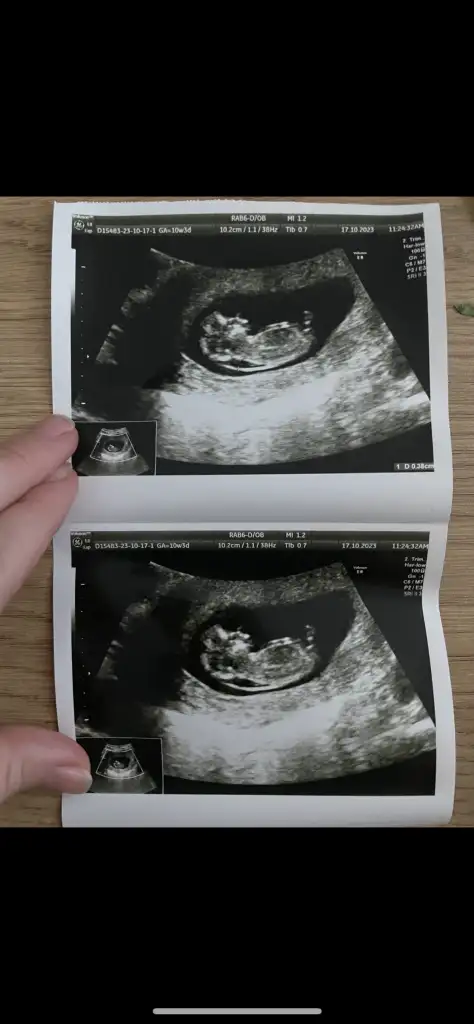

Sırayla 8-12-14 hafta hepsi karından yorumlarsanız sevinirim

12 haftalıkken erkege benziyor denildi 14 hafta kıza benziyor denildi 15 haftalık oldum hala bilmiyorum bebisimin cinsiyetini dahada doktora gitmeme 3 hafta var meraktan çatlamak üzereyim 😅